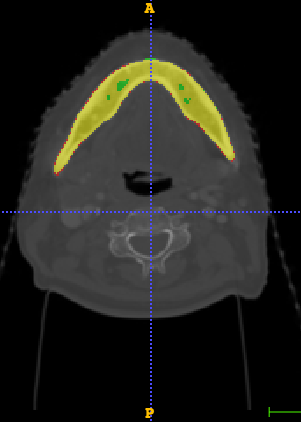

In Chapter 6, we propose an end-to-end, atlas-free 3D convolutional deep learning framework for fast and fully automated whole-volume HaN anatomy segmentation [115]. Our deep learning model, called AnatomyNet, segments OARs from head and neck CT images in an end-to-end fashion, receiving whole-volume HaN CT images as input and generating masks of all OARs of interest in one shot. AnatomyNet is built upon the popular 3D U-net architecture, but extends it in three important ways: 1) a new encoding scheme to allow auto-segmentation on whole-volume CT images instead of local patches or subsets of slices, 2) incorporating 3D squeeze-and-excitation residual blocks in encoding layers for better feature representation, and 3) a new loss function combining Dice scores and focal loss to facilitate the training of the neural model. These features are designed to address two main challenges in deep-learning-based HaN segmentation: a) segmenting small anatomies (i.e., optic chiasm and optic nerves) occupying only a few slices, and b) training with inconsistent data annotations with missing ground truth for some anatomical structures. We collect 261 HaN CT images to train AnatomyNet, and use MICCAI Head and Neck Auto Segmentation Challenge 2015 as a benchmark dataset to evaluate the performance of AnatomyNet. The objective is to segment nine anatomies: brain stem, chiasm, mandible, optic nerve left, optic nerve right, parotid gland left, parotid gland right, submandibular gland left, and submandibular gland right. Compared to previous state-of-the-art results from the MICCAI 2015 competition, AnatomyNet increases Dice similarity coefficient by 3.3% on average. AnatomyNet takes about 0.12 seconds to fully segment a head and neck CT image of dimension , significantly faster than previous methods. In addition, the model is able to process whole-volume CT images and delineate all OARs in one pass, requiring little pre- or post-processing. We demonstrate that our proposed model can improve segmentation accuracy and simplify the auto-segmentation pipeline. These contributions are released as an open-source software package called AnatomyNet, which is publicly available555https://github.com/wentaozhu/AnatomyNet-for-anatomical-segmentation. Portions of this chapter were published as part of [115].

- [121] W. Zhu and X. Xie. Adversarial deep structural networks for mammographic mass segmentation. arXiv:1612.05970, 2016.